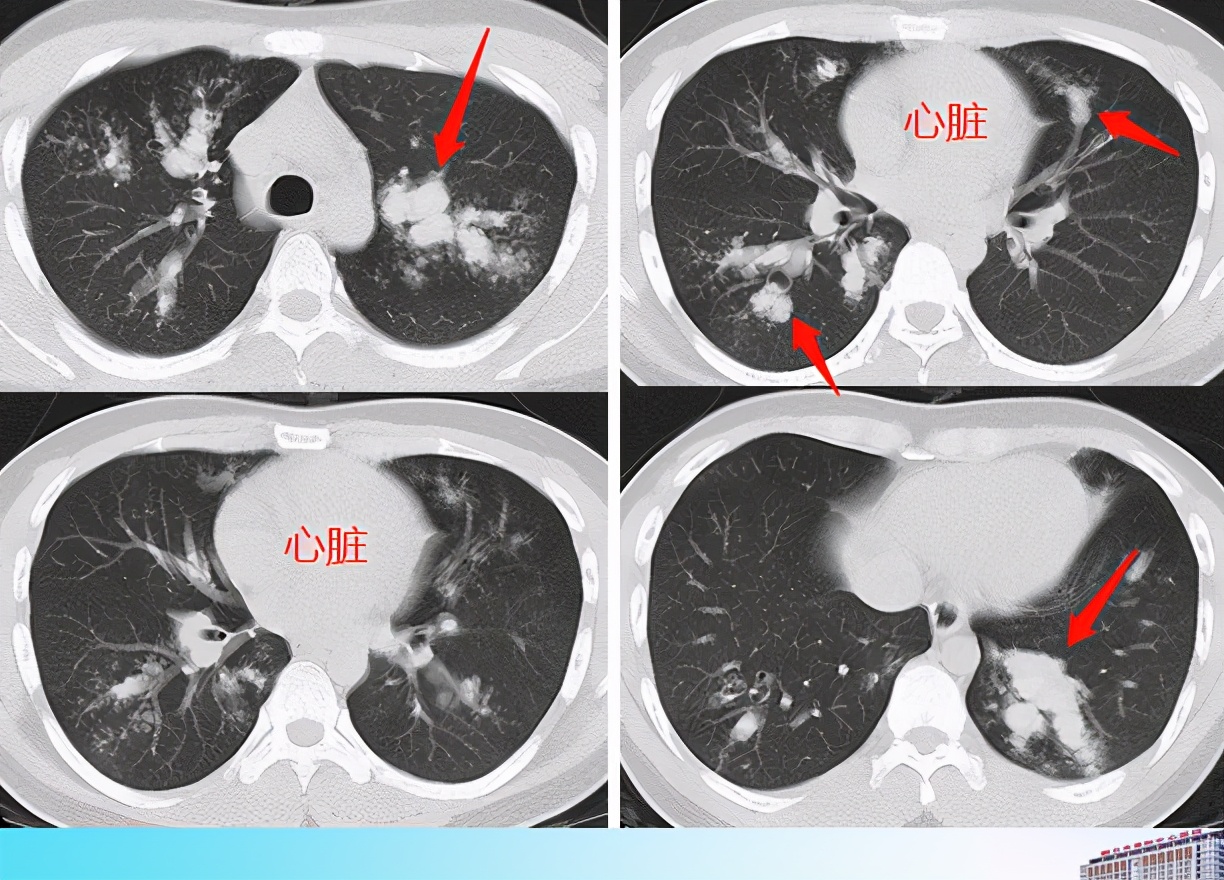

先看一个病例,一位21岁的小伙子,有哮喘病,反复咳嗽咳痰1年,过来做了肺部CT:

病历来自广东省陆丰市人民医院陈华文老师

看上面这4层CT图片,心脏两侧是肺脏,因为含有大量空气,密度低,呈黑色。如箭头所示,在黑色肺组织里可见多发白色迂曲条形影,并且这些条形影与支气管走向一致,提示支气管扩张,并且内部充填很多高密度的病变(粘液栓)。

这种白色迂曲条形影,有人称为指套征,像手指套一样。常见于ABPA、肺癌并支气管粘液栓等。